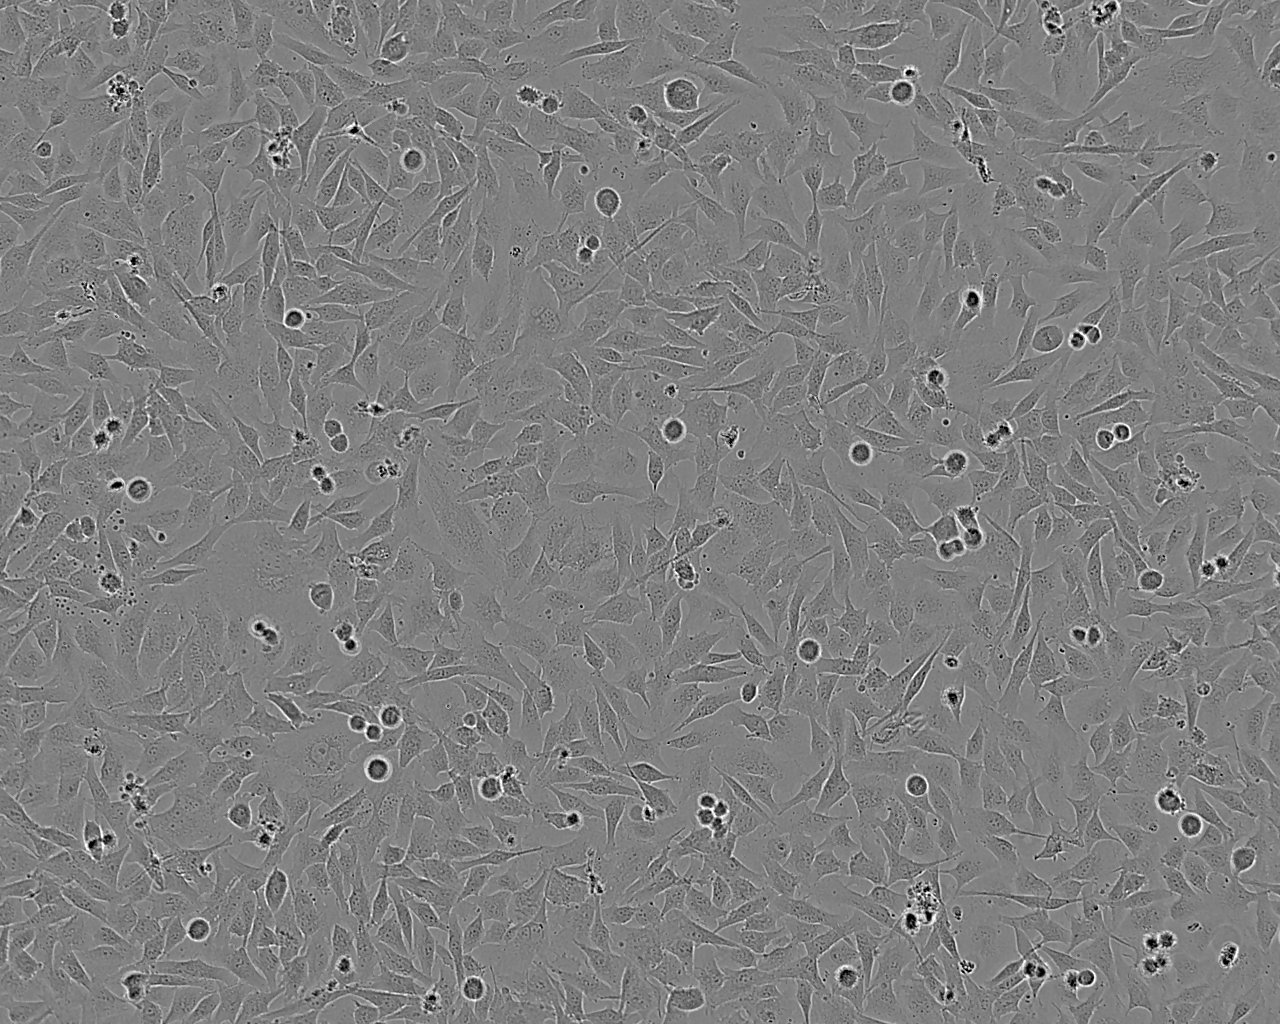

细胞背景资料:未分化甲状腺癌;女性

细胞形态:上皮细胞样

细胞生长:贴壁

细胞生长特性:贴壁